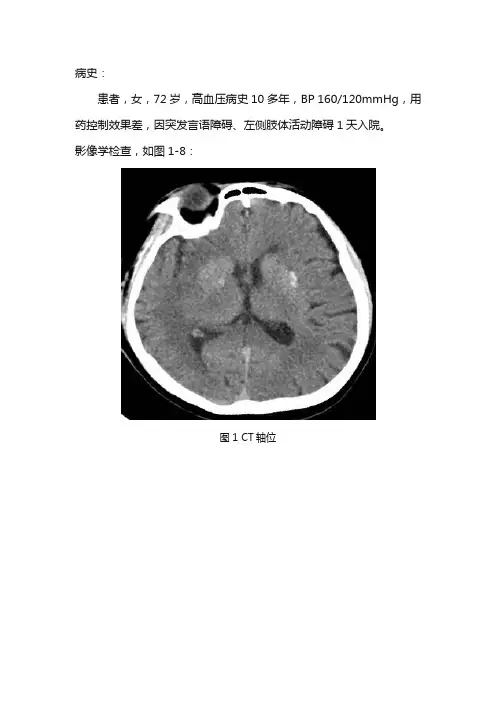

病史:患者,女,72岁,高血压病史10多年,BP 160/120mmHg,用药控制效果差,因突发言语障碍、左侧肢体活动障碍1天入院。

影像学检查,如图1-8:图1 CT轴位图2 CT轴位图3 T1WI轴位图4 T2WI轴位图5 T2WI轴位图6 FLAIR轴位图7 DWI图8 ADC基础解剖影像:图9-13为正常人颅脑主要层面T2WI轴位图片:图9图9为中脑层面,主要包括中脑(黄色箭头),前方为桥前池(棕色箭头),后方为第四脑室(蓝色箭头),颞叶(绿色箭头),小脑半球(白色箭头)。

影像描述:CT右侧颞部脑沟、脑裂变浅,右侧颞叶密度略减低。

MRI双侧颞枕叶、放射冠见斑片状、大片状长T1、长T2异常信号,FLAIR呈高信号,边界欠清。

DWI呈高信号,ADC呈低信号。